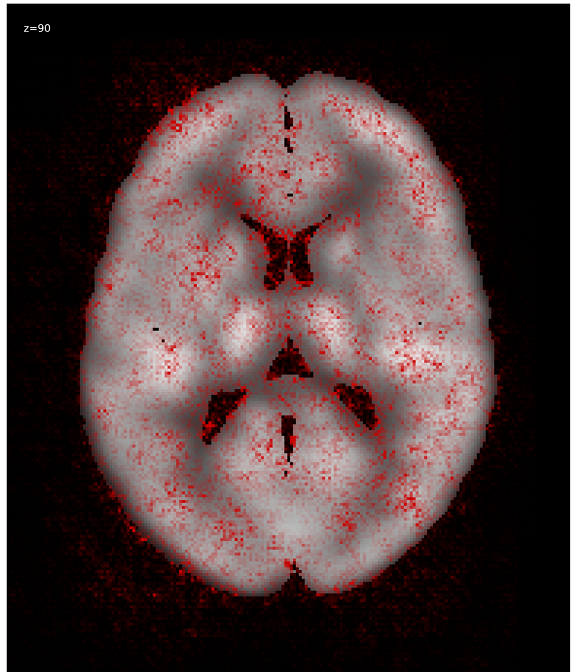

We generated relevance heatmaps for all visualizations methods, averaged over AD PET images in the test dataset. Figure 2 presents the visual comparison of these five methods. The red areas/dots indicate that regions were important for the decision making of the 3D-CNN model. From the result, we can see that all the visualization focuses mostly on similar brain regions. There are some differences, such as the heatmaps generated for the gradient-based methods are distributed. The heatmaps highlight the areas that the CNN network is most susceptible. For the LRP method, the heatmap shows the average relevance of each voxel for contributing to the AD diagnosis score. The heatmaps generated by the occlusion based methods are more focused on the specific regions and cannot administer with large areas of distributed relevance. The reason behind the issue is the occlusion path was not able to cover those areas (for example, the cortex) completely. Brain area occlusion presents very high relevance for the temporal lobe. Since in this method, only one area is covered at a time, that can cause such high importance for one region and minimal relevance for other regions.